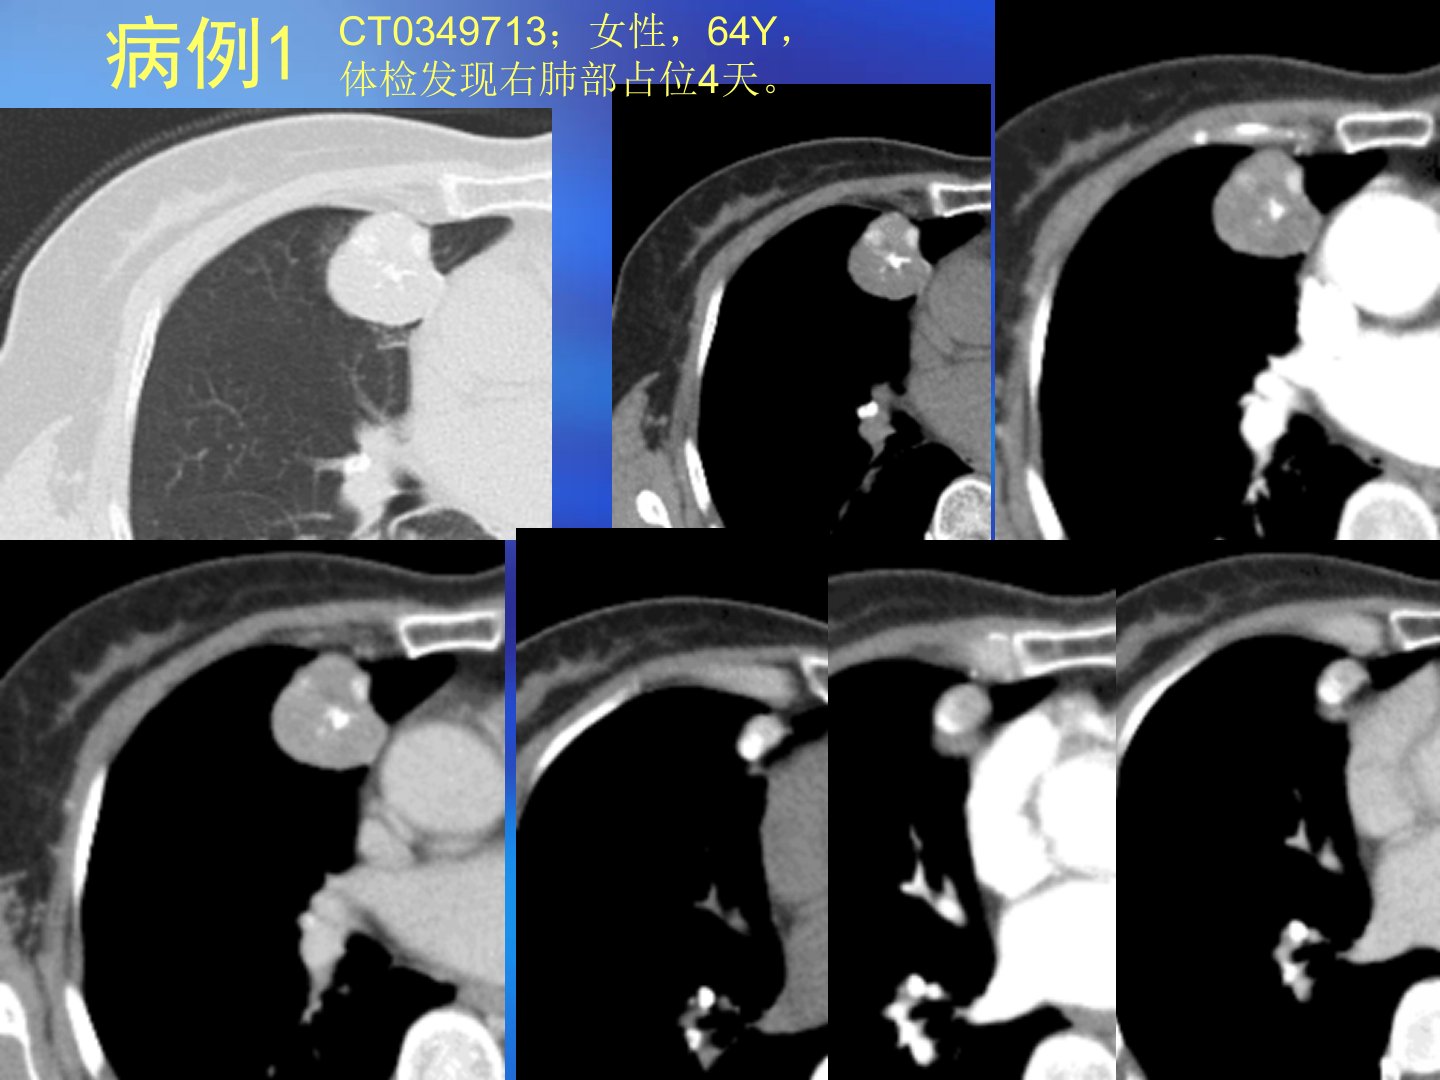

本文汇报了多例肺部占位病例并重点讨论了肺部错构瘤。错构瘤是机体器官内正常组织在发育中出现错误组合导致的类瘤样畸形1904年由德国病理学家albrecht首次提出目前尚无恶变报道。病理特点为正常组织的不正常组合排列构成主要是软骨、脂肪等。根据发生部位错构瘤可分为中央型和周围型WHO将其分为三类。错构瘤好发于40岁以上男性多生长在肺部周边一般无症状刺激或压迫支气管时才会出现相应症状。CT表现上中央型表现为大支气管腔内结节状病变周围型则呈肺内结节样。其CT特点包括边缘光滑、多呈圆形或类圆形、多小于5cm、典型表现为肿块内有脂肪密度区等。鉴别诊断方面需与肺癌、结核瘤、硬化性血管瘤、软骨瘤、转移瘤等区分。